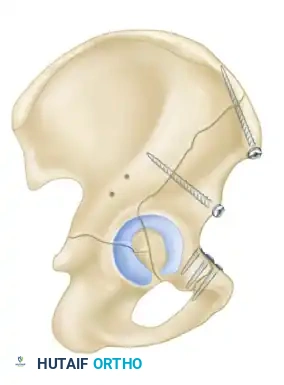

- Anterior Column and Posterior Hemitransverse: An anterior column fracture combined with a transverse fracture through the posterior column.

- Indications: Anterior column, anterior wall, and anterior-dominant both-column fractures.

- Biomechanics: This approach allows for the placement of long reconstruction plates along the pelvic brim (iliopectineal line) to buttress the anterior column.

- Indications: Medial displacement of the quadrilateral surface, anterior column fractures, and certain both-column fractures.

- Technique: A transverse Pfannenstiel incision is made, and the surgeon works intrapelvically, deep to the rectus abdominis and along the pelvic brim. This approach provides direct visualization of the quadrilateral plate and allows for the application of medial buttress plates to prevent medial subluxation of the femoral head. It is frequently combined with a lateral window (from the ilioinguinal approach) for complete anterior column access.